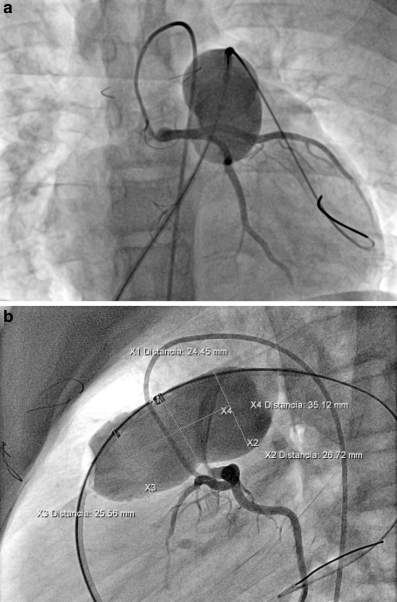

Fig. 3

Sizing balloon interrogation of the right ventricle outflow tract in caudal projection (a) and lateral projection (b) with measurements included. Simultaneously selective left coronary angiogram is observed